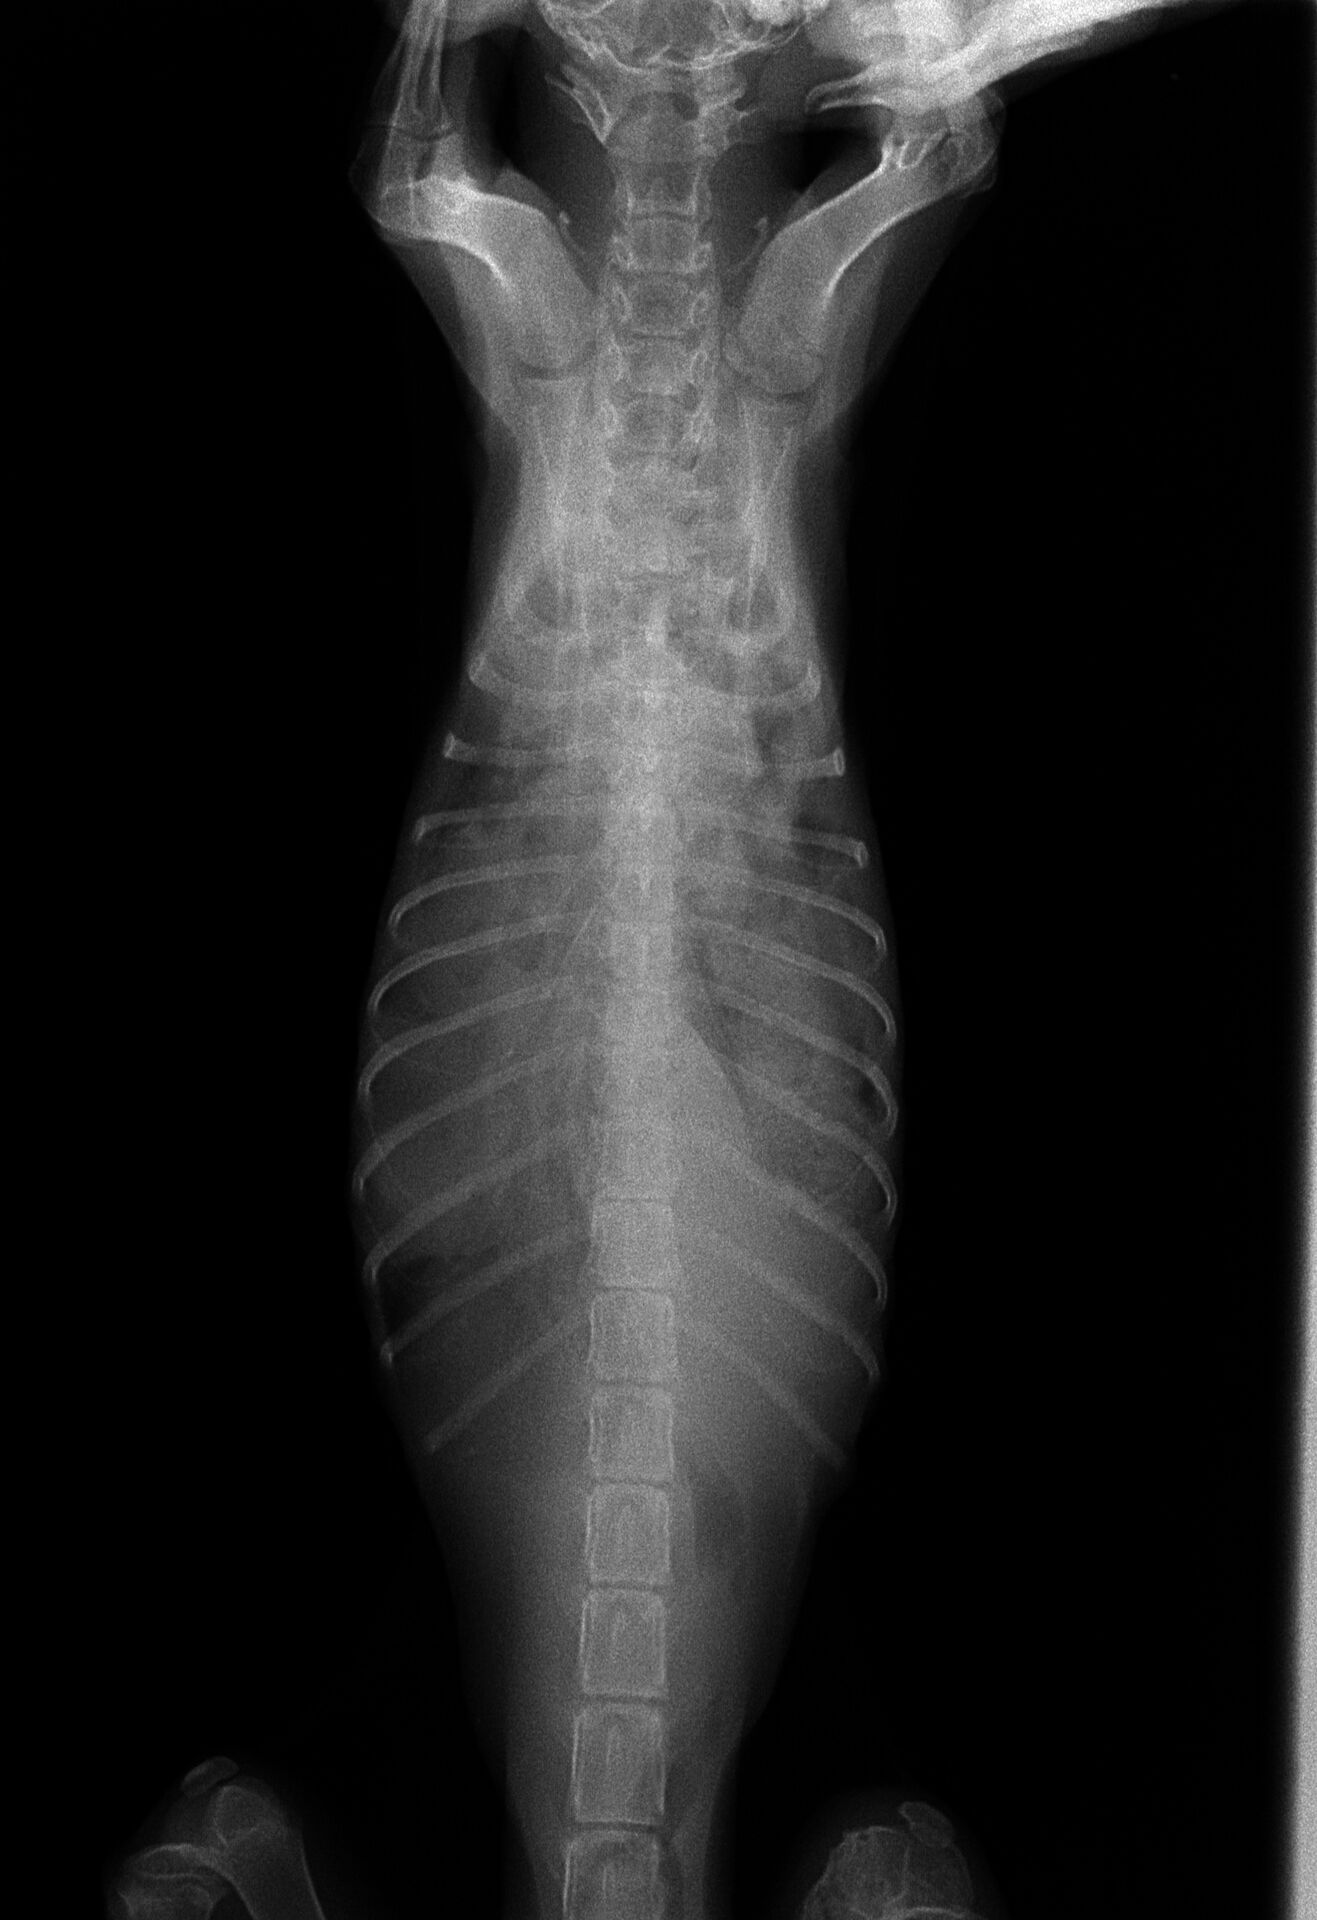

この猫ちゃんは道端で弱っているところを保護された子です。呼吸状態が悪く、脱水状態でもあったのでかなり危険な状態でした。呼吸に異常があると思われたので、レントゲン撮影を行いました。その結果、本来は肺が存在するところに腹腔内臓器である肝臓、胃、腸が入ってしまっています。胸とお腹を分けている横隔膜に穴が開いて、腹腔内の臓器が胸の中に入っている状態です。こうなると肺が満足に膨らまないので、呼吸不全に陥っています。恐らく、交通事故でお腹に車が当たって腹腔内の圧が上がってしまった結果だと思われます。

左右の横隔膜が破れていましたが、右側は肝臓がふたになって肺はほぼ損傷はありませんでした。左側はほとんどの臓器が入って肺は押しつぶされまったく機能していませんでした。